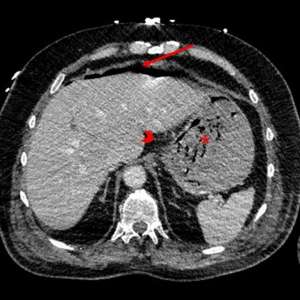

Нетипичный вариант грыжи

Женщина, 77 лет

Обратилась в отделение неотложной помощи с жалобами на боль в животе, тошноту и рвоту, которые беспокоили её в течение двух дней. При осмотре выявлено вздутие живота и болезненность в левом нижнем квадранте.

Обнаружено грыжевое выпячивание ниже паховой связки, латеральнее лобкового симфиза и медиальнее общих бедренных сосудов со сдавливанием бедренной вены, содержащее петли подвздошной кишки.